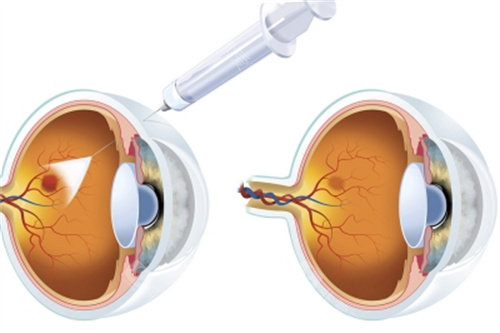

余锦强医师是玻璃体视网膜疾病领域的显要,尤其擅长复杂性视网膜脱离、糖尿病视网膜病变的小创口玻切手术,手术精细度高,视功能重建改善显著。华远锋副高医师则在眼外伤急诊处理方面技术娴熟,能够及时救治眼球破裂伤等急症,更大限度保留患者眼球结构和功能。